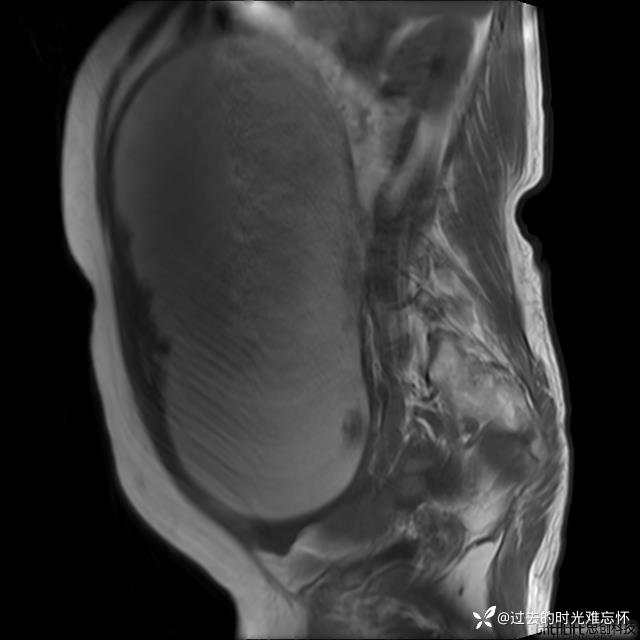

患者性别:女

患者年龄:65岁

主诉: 发现腹部隆起半年余。无其他明显不适。

浆液性囊腺瘤 (22)